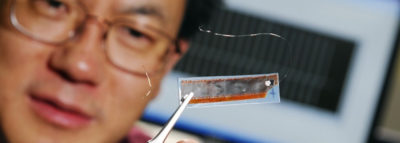

Biologisch abbaubare Materialien finden immer stärker ihren Einsatz in Architektur und Design. Nun schwappt das Thema auch in die Elektronik-Branche. Materialwissenschaftler der Carnegie Mellon University haben eine Batterie entwickelt, die kleine elektronische Pillen mit Strom versorgen und nach ihrem Einsatz vom Körper abgebaut werden kann. Damit könnten bestimmte Medikamente effektiver verabreicht und wichtige Körperfunktionen von innen heraus gemessen werden.

Die Bio-Batterie benutzt als Anode das Pigment Melanin, welches der Tinte der Sepien ihr schwarze Färbung verleiht. Die Kathode ist Manganoxid, welches ebenso problemlos vom Körper in nicht-toxische Reststoffe abgebaut werden kann. Das Projekt könnte ein wichtiger Baustein sogenannter „smart pills“ werden, die mit Sensoren bestückt im Körper Heilungsprozesse überwachen, wohldosiert Medikamente ausschütten oder gar Blutgefäße und Nerven stimulieren. Zwar leisten diese Batterien nicht so viel wie vergleichbare Lithium-Ionen-Batterien, was für beschrieben medizinische Zwecke aber auch gar nicht notwendig ist.

Foto: Alexander Semenov